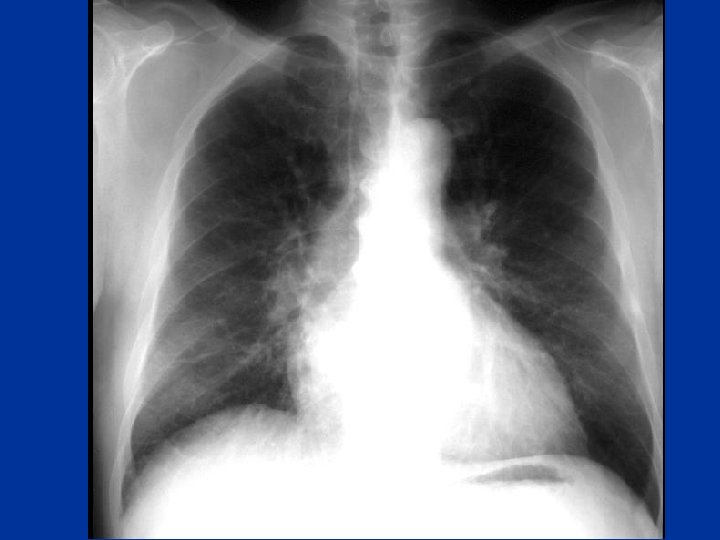

Pneumothorax • tall, thin, young patient. H/O pleural aspiration or biopsy • Symptoms: wheezes • one hemithorax • Hyperinflated • Hyperresonance • ↓ breath sounds • Trachea + mediastinal shift • CXR esp • exp. film

Pneumothorax • Major Types: • Spontaneous: Primary peak 20 -30 yrs, 4: 1 male : female • Tall thin , cigarette smokers, positive family history Secondary: Parenchymal lung disease e. g sarcoidosis, IPF, Emphysema, Necrotising pneumonia incl. Tb, PCP, • Iatrogenic: Pleural tap, transbronchial lung biopsy, positive pressure ventilation. • Traumatic: Rib fracture, bronchial rupture, esophageal rupture

Pneumothorax Mechanism • rupture of subpleural bleb or parenchymal process eroding visceral pleura this may also cause partial bronchial obstruction(check -valve mechanism) & hyperinflation